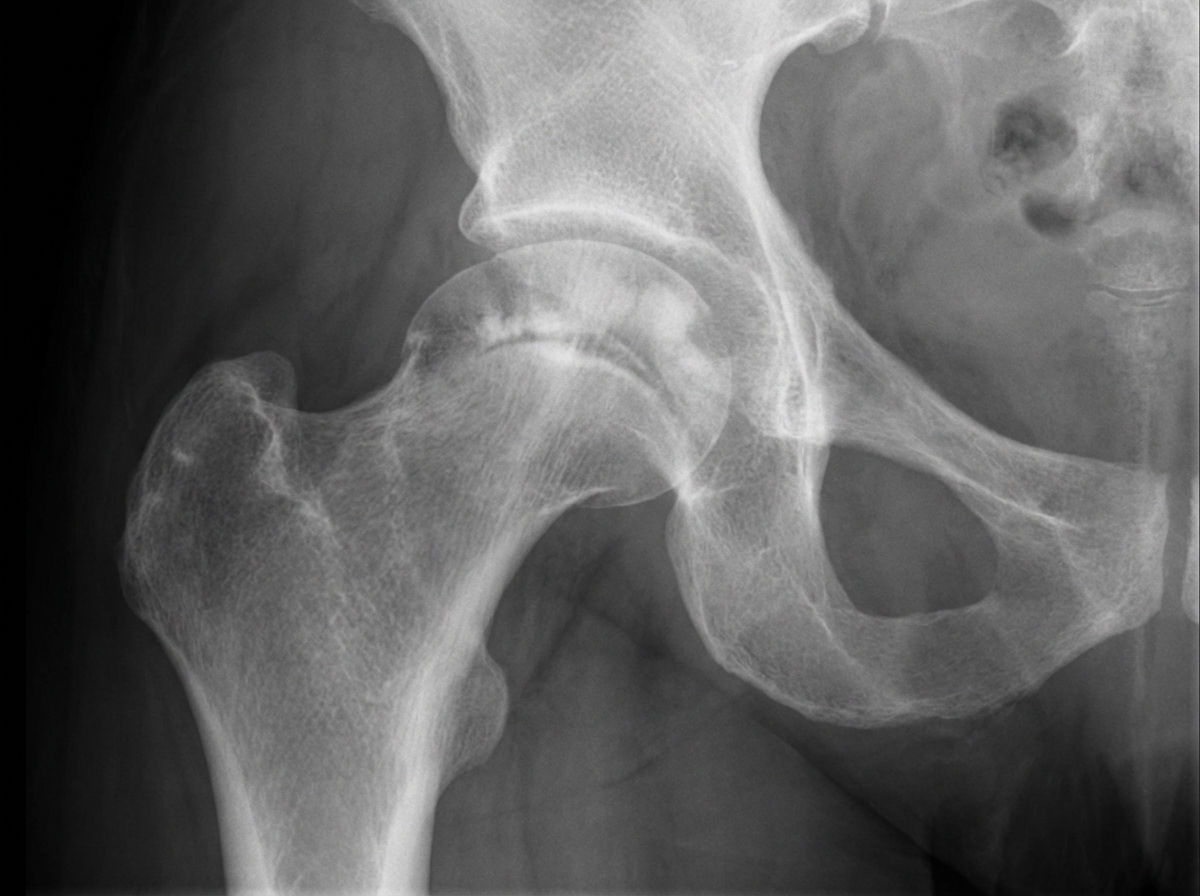

A 36-year-old woman with sickle cell disease presents with increasing pain in her right hip. She has no fever, chills, back or other bone pain, and there is no history of any trauma. On examination, her temperature is 37.3°C, range of motion in the right hip is reduced, she walks with a limp, and the right leg is shorter than the left. Movements of the hip and walking on it are painful. X-rays of the hip are shown. Which of the following is the most likely diagnosis?

Explanation: ***Avascular necrosis (AVN) of the femoral head*** - **Sickle cell disease** predisposes to AVN due to **vascular occlusion** from sickling of red blood cells, leading to bone infarction and necrosis of the femoral head. - Clinical presentation of **reduced hip range of motion**, **leg length discrepancy**, and **painful walking** without fever are classic signs of AVN in sickle cell patients. *Osteomyelitis* - Typically presents with **systemic symptoms** including high fever, chills, and elevated inflammatory markers, which are absent in this case. - **Sickle cell patients** are prone to osteomyelitis, but the lack of fever and normal temperature make this diagnosis less likely. *Hip fracture* - Requires a **history of trauma** or significant force, which is explicitly absent in this patient's presentation. - **X-ray findings** would show clear fracture lines rather than the changes typical of avascular necrosis. *Septic arthritis* - Usually presents with **high fever**, **acute onset** of severe pain, and **systemic toxicity**, none of which are present here. - The **gradual onset** and **absence of fever** make septic arthritis unlikely despite the patient's underlying sickle cell disease.